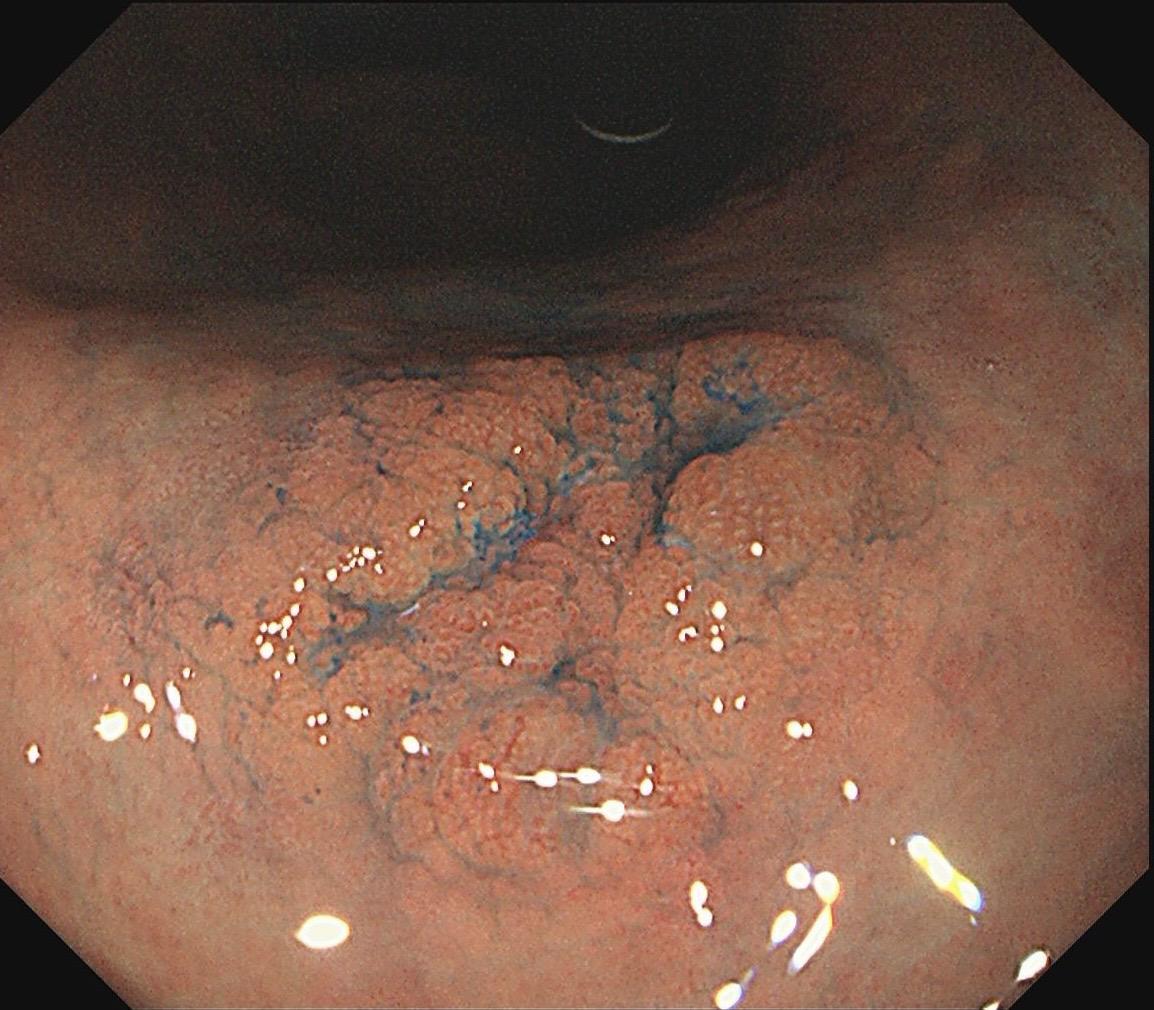

女,57岁,胃角。同事熟人,萎缩背景,色调淡黄,中央浅凹陷,腺管小而密集。